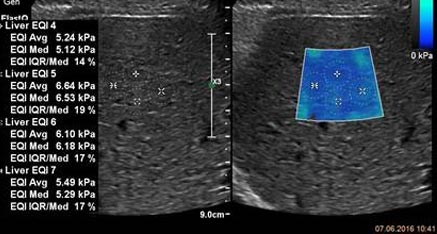

Известно, что результаты ультразвуковой количественной оценки степени жесткости печени зависят от производителя. Понимая эту проблему, компания Philips прикладывает все усилия чтобы клиническое сообщество получало самую точную и клинически достоверную информацию.  При партнерстве с Российской ассоциацией специалистов ультразвуковой диагностики в медицине и ведущими экспертами кафедры ультразвуковой диагностики Университета Павии (Италия) были подготовлены рекомендации с целью стандартизации оценки жесткости печени на ультразвуковом оборудовании компании Philips

Рекомендации РАСУДМ по проведению эластографии сдвиговой волной для оценки жесткости печени при использовании ультразвуковых аппаратов компании Филипс с примером протокола

Клинические изображения различных стадий фиброза печени

Изучите клинические примеры неинвазивной оценки фиброза печени.

Клинические случаи

Вашему вниманию предоставляются клинические случаи фиброза печени.

Эластография

Новые возможности эластографии в сочетании с превосходным качеством изображений позволяют использовать менее инвазивные и менее дорогостоящие методы получения данных при диагностике заболеваний печени.